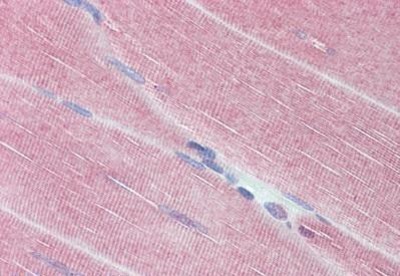

Supportive validation

- Submitted by

- Novus Biologicals (provider)

- Main image

- Experimental details

- Immunohistochemistry-Paraffin: Myosin Phosphatase Antibody [NBP1-52478] - Analysis of anti-PPP1R12A / MYPT1 antibody with human skeletal muscle at concentration 3.75 ug/ml.